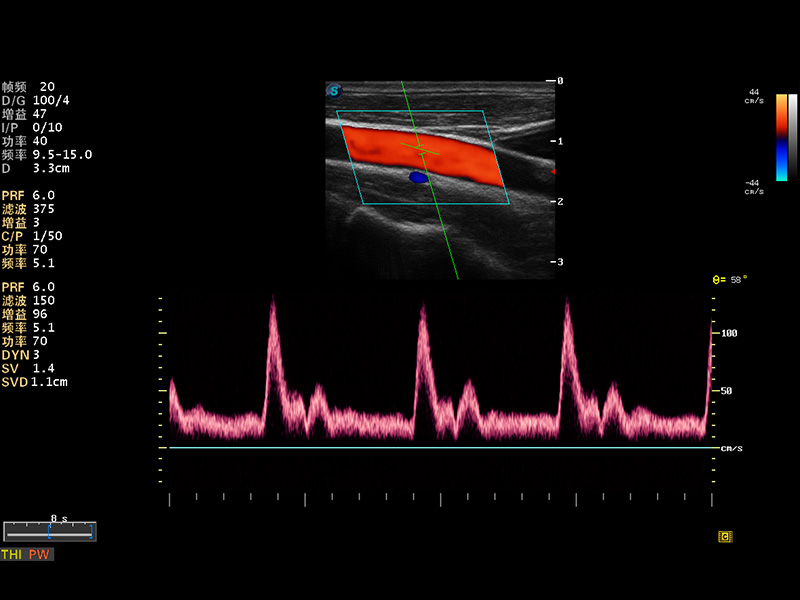

S8 EXP便携式彩色多普勒超声诊断仪是百老汇电子游戏官网研发的高端全身应用型便携彩超。高通道的VIS平台融合可视化(Visual)、智能化(Intelligent)和人性化(Smart)的特点,配以百老汇电子游戏官网自主研发生产的探头大家族,使您能够快速、准确的获得病人信息,提高工作效率的同时减轻疲劳。

多波束形成器

μ-Scan微米成像